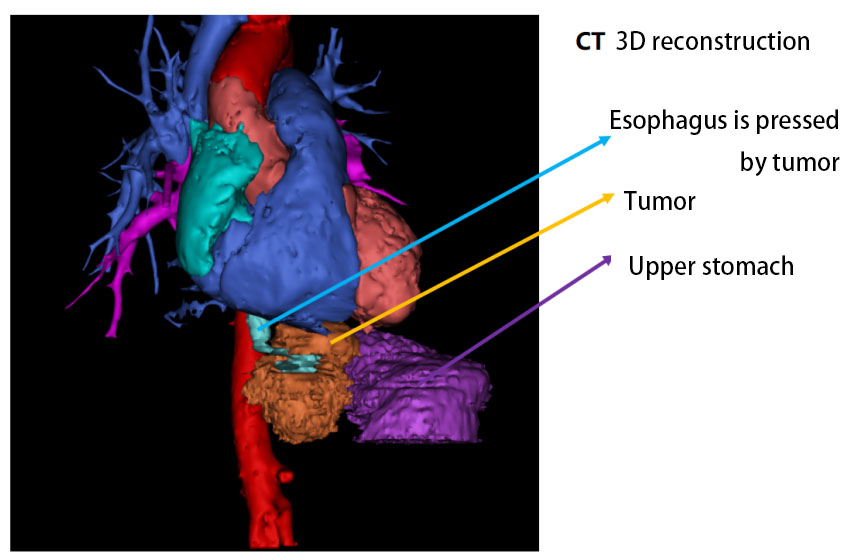

The 3D reconstruction indicates that a large tumor encircles the esophagus and it is adjacent to the aorta. The tumor has a "hoof-shaped" around the junction of the esophagus and the cardia, with the major axis measuring approximately 6.4 cm and the minor axis measuring approximately 3.7 cm.

The tumor resembles a dumbbell encircling the upper segment of the esophagus.